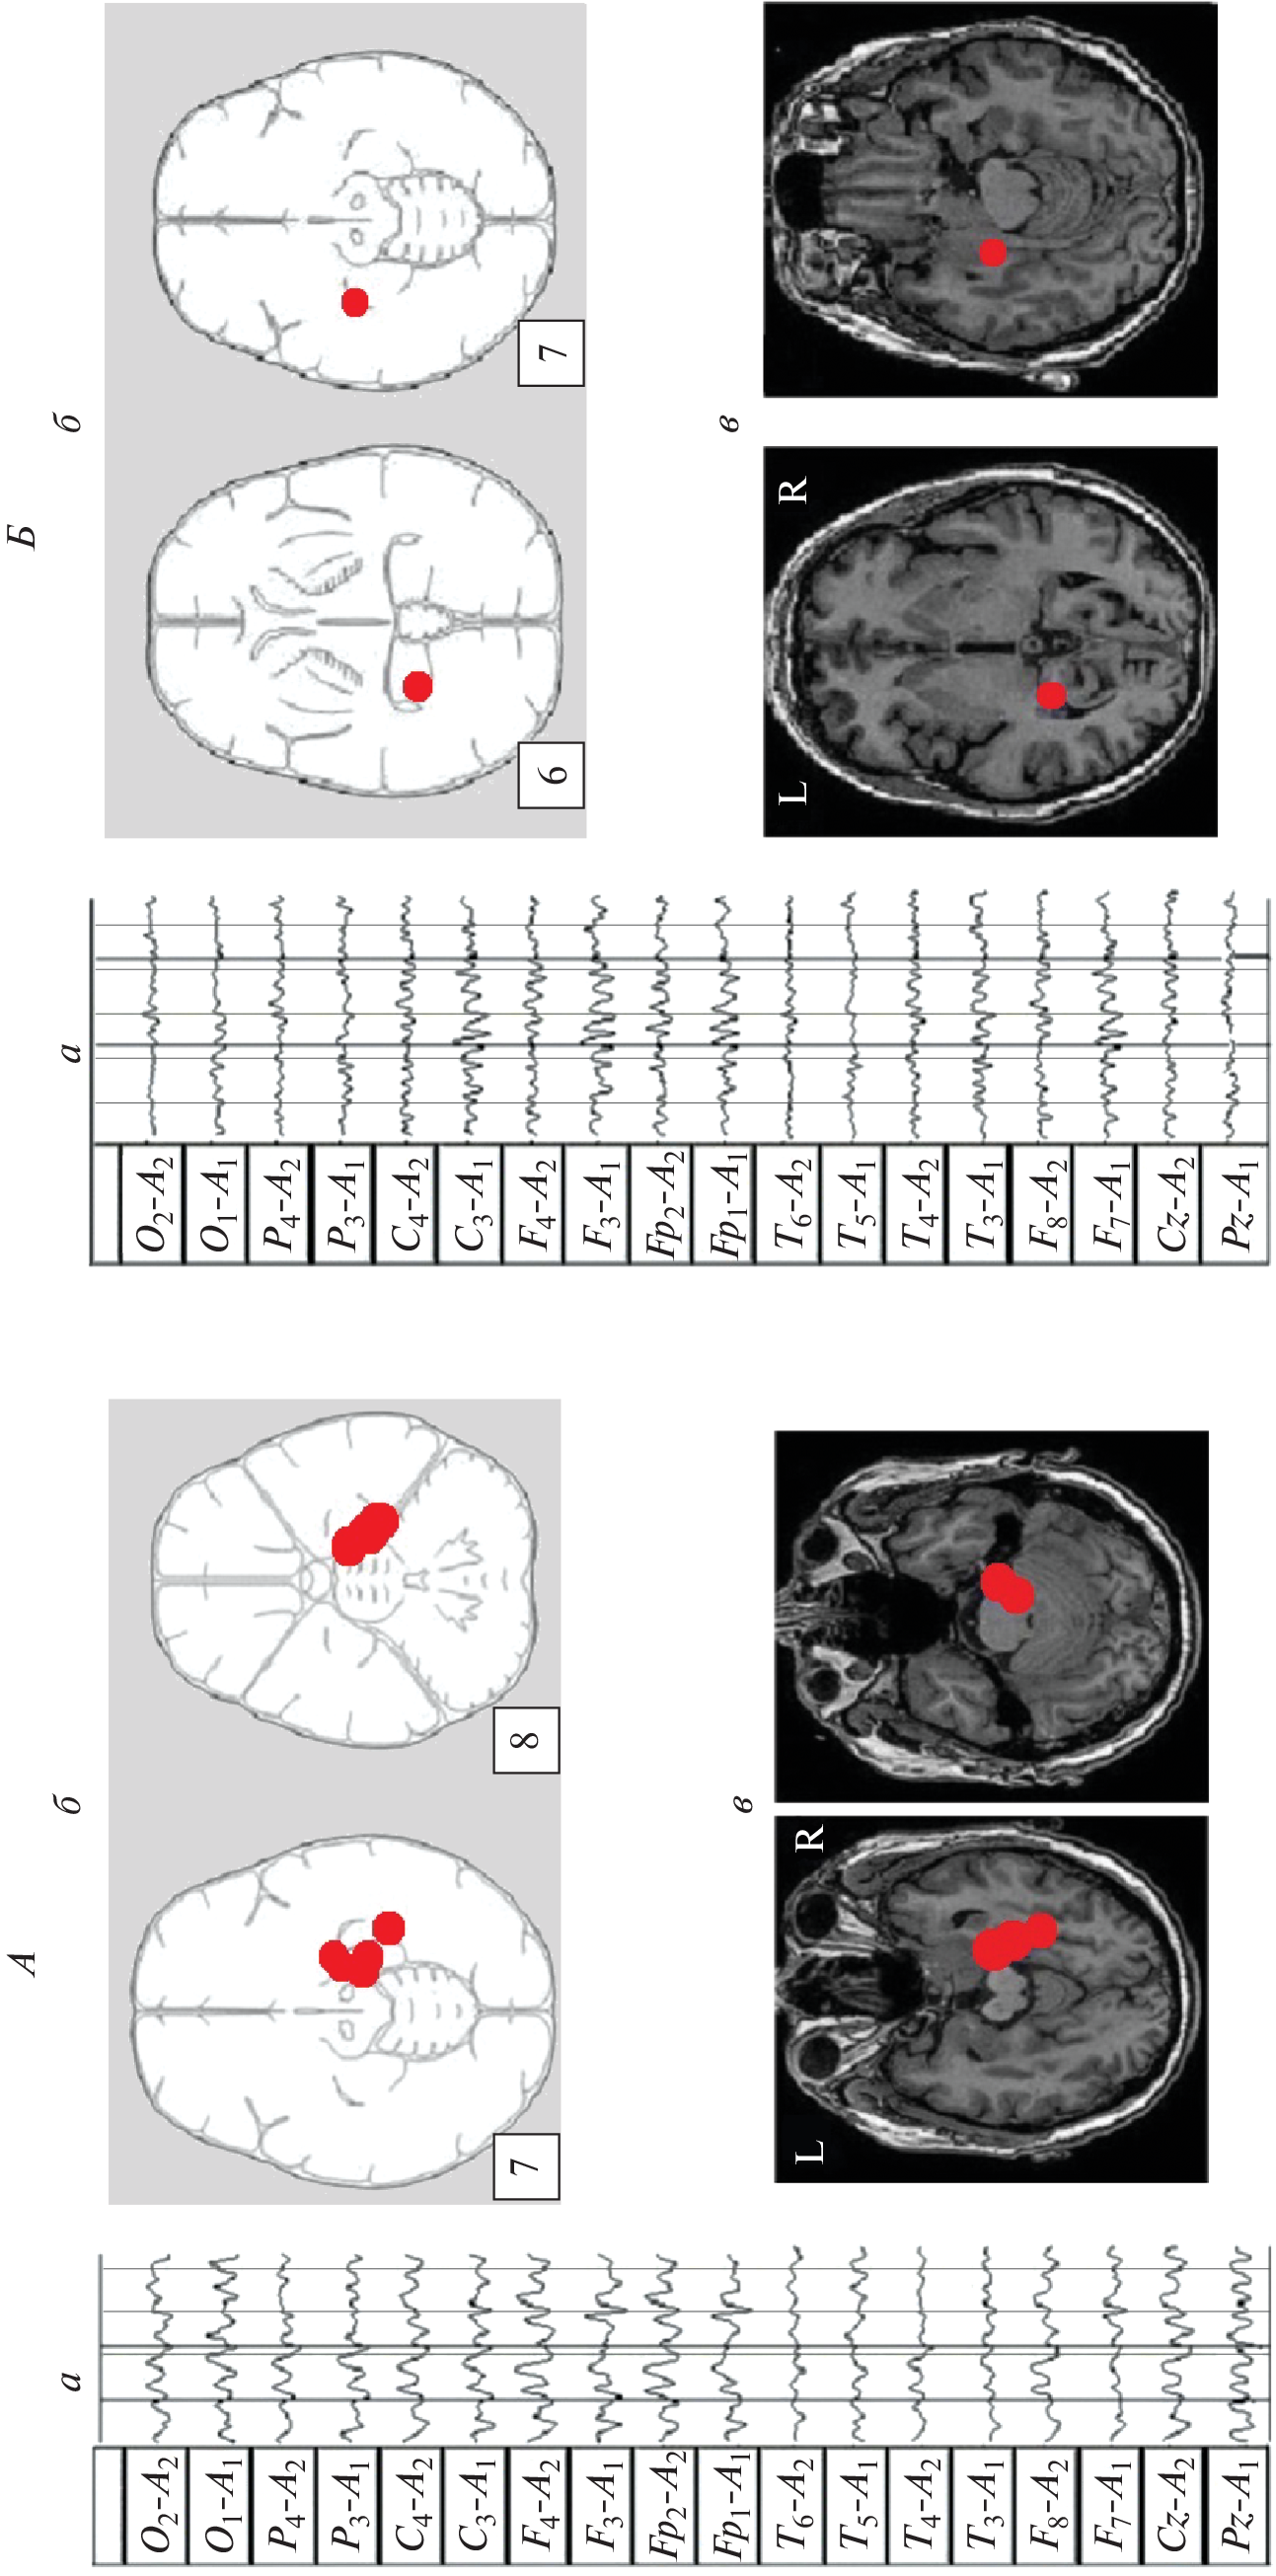

We studied the features of EEG and visual memory processes in 27 patients with a mediobasal regions extracerebral tumor of right and left hemispheres. According to neuroimaging (MRI) and morphometry, the degree of hippocampus involvement in pathological process was assessed. The predominant concentration of irritative-epileptiform signs in the affected hemisphere, as well as the presence of atypical alpha-rhythm episodes in the tumor projection zone, were classified as EEG markers of tumor compressive effect on the hippocampus. Signs of non-identical involvement of the right and left hippocampi in the pathological process were found in the form of a predominance of irritative signs in the left hemisphere throughout the group as a whole. Equivalent dipole sources (EDS) of atypical alpha rhythm are more confined to hippocampal structures than irritative EEG patterns. Neuropsychological testing of visual memory did not reveal significant disturbances in memory processes at this stage of the disease.

- Коптелов Ю.М., Гнездицкий В.В. Анализ “скальповых потенциальных полей” и трехмерная локализация источников эпилептической активности мозга человека // Журн. неврол. психиатр. им. С.С. Корсакова. 1989. Т. 89. № 6. С. 11. Koptelov Yu.M., Gnezditskii V.V. [Analysis of scalp potential fields and the three-dimensional localization of sources of epileptic activity in the human brain] // Zh. Nevrol. Psikhiatr. Im. S.S. Korsakova. 1989. V. 89. № 6. P. 11.

- Болдырева Г.Н. Атипичные формы церебральной альфа-активности при поражении регуляторных структур мозга человека // Физиология человека. 2018. Т. 44. № 3. С. 14. Boldyreva G.N. Atypical forms of cerebral alpha activity when human brain regulatory structures are damaged // Human Physiology. 2018. V. 44. № 3. P. 246.

- Болдырева Г.Н., Шарова Е.В., Коптелов Ю.М. и др. Исследование генеза патологических паттернов ЭЭГ при опухолевом и травматическом поражении мозга человека // Физиология человека. 2005. Т. 31. № 1. С. 24. Boldyreva G.N., Sharova E.V., Koptelov Yu.M. et al. Study of the genesis of pathological EEG patterns in tumor and traumatic lesions of the human brain // Human Physiology. 2005. V. 31. № 1. P. 18.

- Фролов А.А., Болдырева Г.Н., Коптелов Ю.М. Поиск источников патологической альфа-активности ЭЭГ человека при поражении лимбических структур // Журн. высш. нерв. деят. им. И.П. Павлова. 1998. Т. 48. № 4. С. 687. Frolov A.A., Boldyreva G.N., Koptelov Yu.M. [Sources of pathological EEG alpha-activity in patients with lesions of limbic structures] // Zh. Vyssh. Nerv. Deiat. Im. I.P. Pavlova. V. 48. № 4. P. 687.